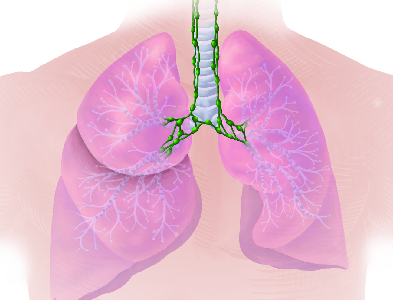

Detailreiche Fotografien aus der medizinischen Praxis ergänzen die Texte; moderne, genaue,

wissenschaftliche Zeichnungen geben Einblick in die Anatomie und die Funktion der Lunge und

anderer Organe.